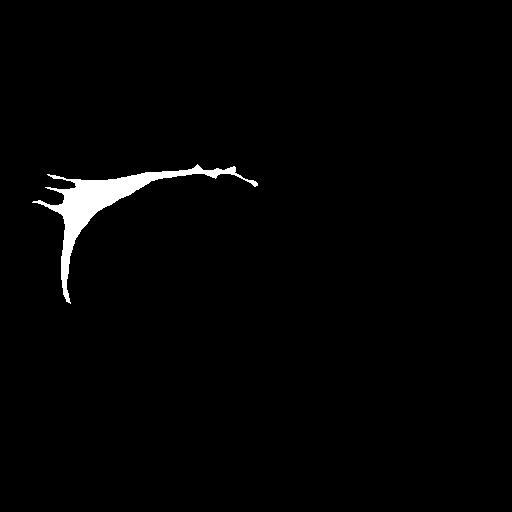

3.5 Failure Cases

In Figure 3, we illustrate failure cases in dataset . In the first example, AURA-net fails to correctly segment the bottom part of the object. This outcome is unsurprising considering that the raw image exhibits a lower SNR than any of the training data. In the second example, the segmentation mask predicted by AURA-net contains several objects, yielding a poor overlap with the ground truth annotation featuring a single cell. However, the original image reveals the presence of a second, partially cropped non-annotated cell. In this case, part of AURA-net’s “false” detection are actually correct predictions that have been omitted in ground truth annotations.